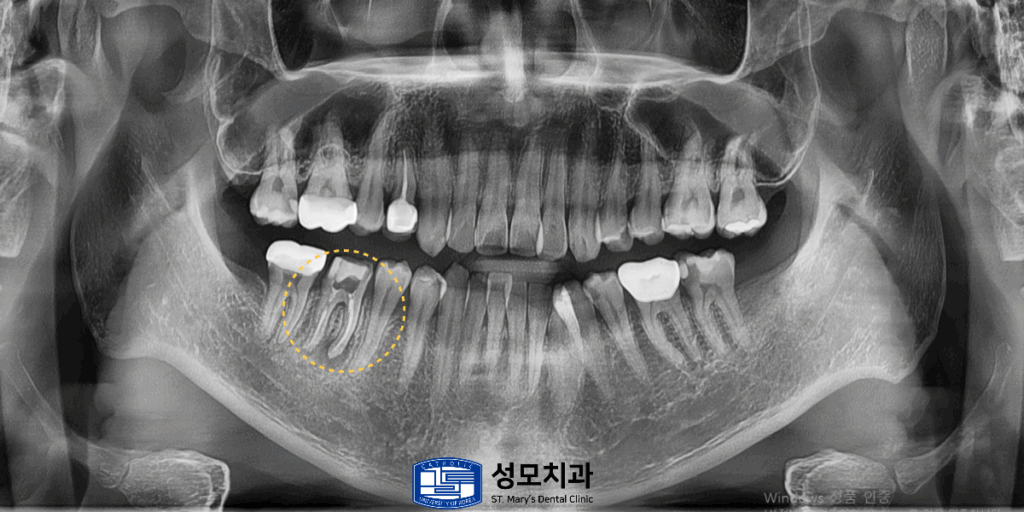

전체 파노라마 x-ray를 촬영하여

상태를 확인해 보았습니다.

x-ray 사진을 통해 확인한 결과

표시된 치아 치근단 부위에 뚜렷한

염증 병소가 관찰되었습니다.

또한 기존 근관치료의 마무리가 부족하여

세균이 재유입된 것으로 판단하였습니다.